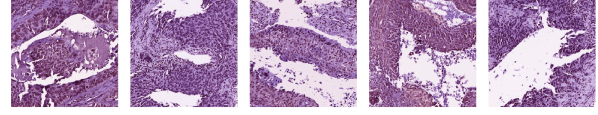

Appendix D Cluster Visualization

| Cluster 2 () |

| Cluster 40 () |

| Cluster 48 () |

| Cluster 11 ( |

| Cluster 15 ( |

| Cluster 34 ( |

| Cluster 23 ( |

| Cluster 43 () |